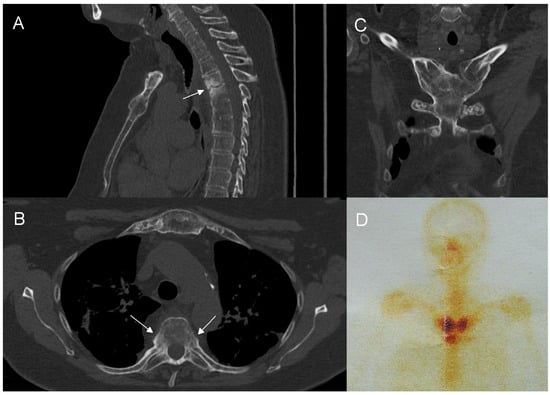

Figure 4.

Imaging findings of the thoracic spine involvement in a 65-year-old patient with SAPHO syndrome. CT (A) shows multilevel, contiguous vertebral osteosclerosis, endplate erosions, and early syndesmophyte formation. MRI (B) shows diffuse and propagating patterns of BME and mild prevertebral soft tissue inflammation.

In adults, the main findings were BME, osteosclerosis, endplate irregularities, and a spectrum of ankylosing lesions. Similar to previous publications, the lesions were multilevel and contiguous [21,22,32,33]. Curvilinear/semicircular pattern of BME found in the majority of patients in the study by McGvuran and coworkers was less common in our material three patients); however, both BME and osteosclerosis overlapping BME on plain film/CT were definitely the most striking abnormalities (Figure 4) [22]. We also observed a long persistence of BME that was present through the whole length of follow up, even in patients followed for more than 10 years. On MRI, contrast enhancement was observed in the areas of BME, but also in the linear fashion along the endplates and frequently in the non-ankylosed costovertebral and facet joints. Paraspinal soft tissue involvement was observed in 10 out of 12 patients subjected to MRI (83%), more often than in previous publications [22,34]. In agreement with previous reports, most of the intervertebral discs showed decreased T2 signal corresponding to degeneration rather than the high signal seen in discitis [22]. Vertebral deformities were limited to anterior wedging, most pronounced at the apex of thoracic kyphosis. Ankylosing lesions were prevalent and, as previously reported, showed a progressive character on follow up [35,36]. Anterior bony bridging resembling this observed in diffuse idiopathic skeletal hyperostosis (DISH) was accompanied by intervertebral fusion and facet joint ankylosis. Contrary to previous reports, we have not observed the resolution of hyperostosis once ankylosis was complete [36].